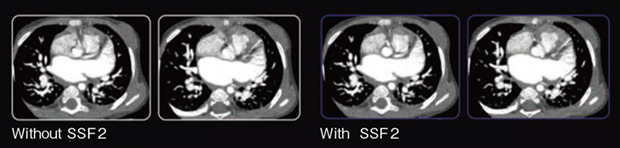

・心臓弁・大血管の動き補正(図2)

図2 大動脈弁におけるSSF2の効果

SSF2使用により石灰化の評価・弁輪系の計測精度が向上している。